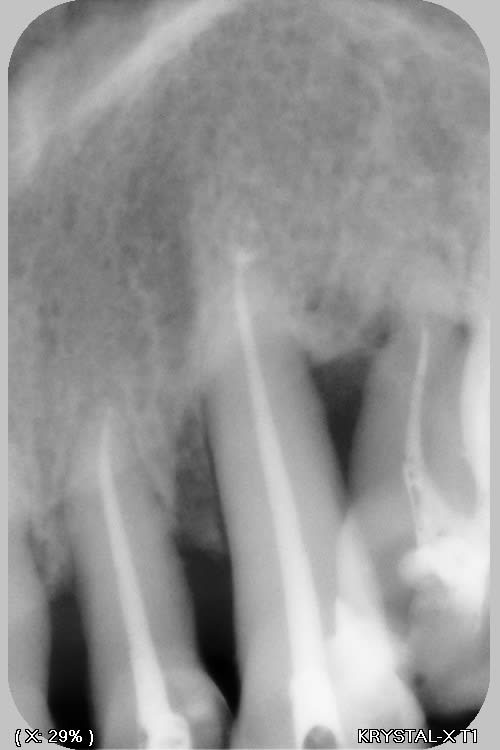

j'ai trouvé ça...rien de parfait malgré l'utilisation de broches manuelle, en alternance avec les rotatives sur certaines racine "légèrement coudées"....

pano et scan plus tard